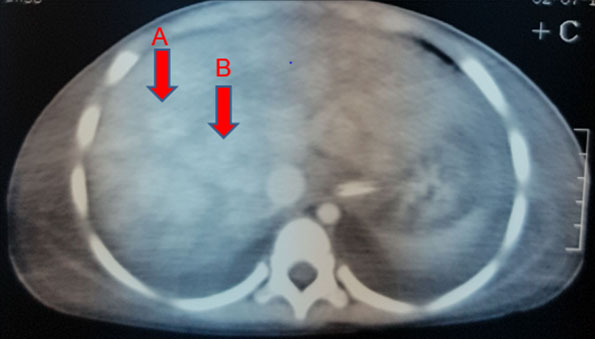

Initial investigation profile showed hemoglobin (Hb) of 8.5 g/dL with microcytosis and hypochromia. Some atypical lymphocytes and increased platelets were noted. Blood culture grew Staphylococcus aureus sensitive to penicillin. Erythrocyte sedimentation rate (ESR) using the Westergrens method was normal (20 mm/h). Reticulocytes were 7.9%. Hepatitis and venereal disease research laboratory (VDRL) serology were negative. Pleural aspirate had red cells with 1600 white blood cells/mm3 which reduced to 320 white blood cells/mm3 on a repeat tap five days later. Biochemistry analysis [glucose 6.7 mmol, total protein 1 g/L, albumin 18, lactate dehydrogenase (LDH) 234 U/L] showed effusion was transudative in nature. No malignant cells seen. Culture was negative and no acid-fast bacilli (AFB) were seen. Ascitic fluid also had red blood cells and 160 white cells/ mm3, cultures were negative, glucose 6.7 mmol, total protein 19 g/L, Alb 10.2 g/L, LDH 234 U/L. The serum ascites albumin gradient was >1.1 g/dL indicating portal hypertension, negative for malignant cells. Her liver functions deteriorated over the course of admission. Antinuclear antibodies (ANA) and double stranded DNA (DsDNA) done to rule out SLE were also negative. Computed tomography (CT) scan revealed multifocal segments of venous thrombosis involving right internal jugular vein (Figure 3), left brachiocephalic, main portal vein, superior mesenteric, and hepatic veins. There was no obvious neck thoracic or abdominopelvic mass. Moderate ascites were with bilateral pleural effusion. Liver showed inhomogeneous enhancements/nutmeg liver with thrombosis of hepatic veins (Figure 4). Liver biopsy was contemplated, however poor general condition and deranged coagulation profile precluded the invasive procedure.

Figure 4: Contrast CT scan of liver showing inhomogeneous enhancements/nutmeg liver appearance (A), with thrombosis of hepatic veins (absence of contrast in portal veins) (B).